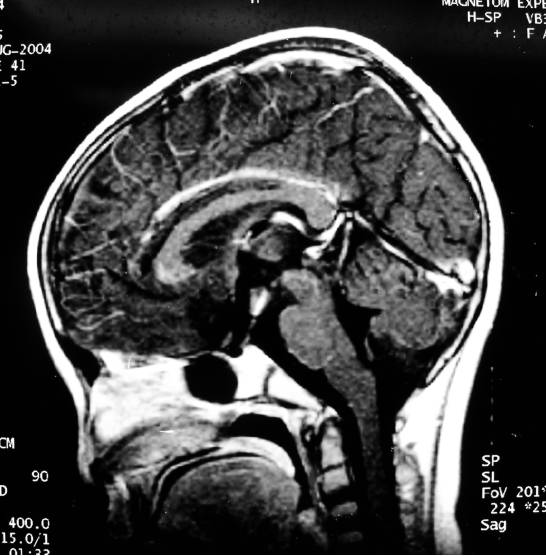

至术后第7天,患儿突发呕吐,抽搐两次,伴意识模糊,体温39.7℃,头颅CT复查未见明显异常。查血电解质:K+ 4.35mmol/L, Na+116mmol/L,Cl-77mmol/L,立即给予静脉补钠144.5mmol,同时给予解痉降温等对症处理,5小时后复查:K+5.09mmol/L,Na +119mmol/L,Cl-85mmol/L,再次予静脉补钠106mmol。第8天复查电解质无明显变化,K+ 3.82 mmol/L ,Na+115mmol/L,Cl-84mmol/L。继续补Na+ 174.25mmol。第9天K+4.13mmol/L,Na+130mmol/L,Cl-99mmol/L,补钠量减为68mmol。第10天,K+3.89mmol/L,Na+165mmol/L,Cl-133mmol/L.即停止补钠,并予补液处理。第11天恢复正常,K+4.17mmol/L ,Na+147mmol/L,Cl-110mmol/L。之后继续监测电解质均维持在正常范围,但体温一直偏高,波动于38.2-39.6℃之间,意识模糊。予鲁米那等对症处理。术后第20天,出现四肢肌肉粗震颤,以左上肢明显,并且反应淡漠。第27天,双下肢和左上肢呈肌强直,复查垂体激素正常。头颅MRI检查提示:双侧尾状核和壳核对称性长T1,长T2信号改变(图3),考虑为脱髓鞘变。

图3. 术后27天,双侧尾状核和壳核在MRIT1加权像上呈低信号,MRIT2加权像上呈高信号。